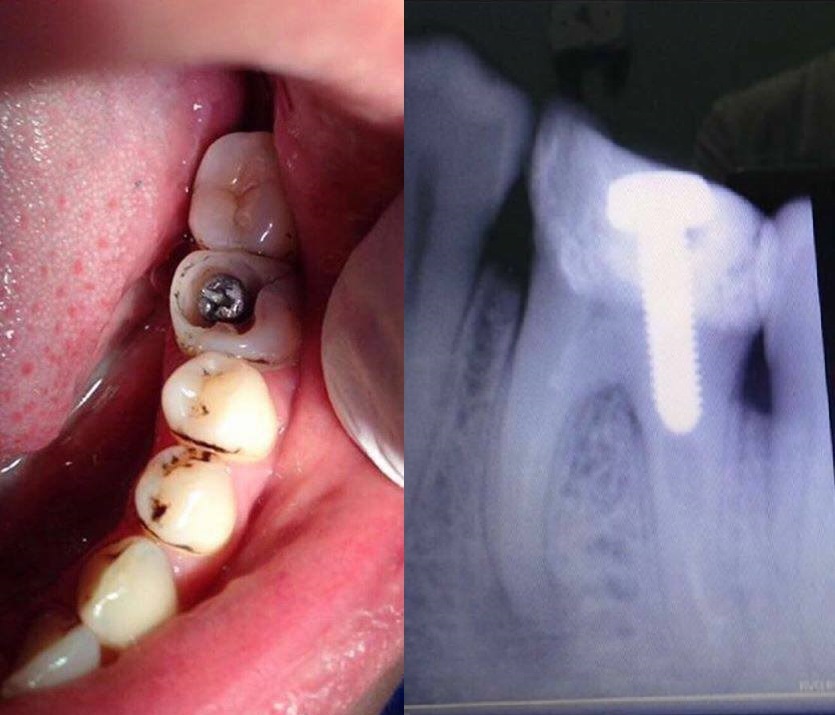

Parafuso ou Implante?

Procure no site do Conselho Federal de Odontologia http://cfo.org.br/servicos-e-consultas/profissionais/ para saber se o profissional está cadastrado para que não aconteça como no caso abaixo, onde foi colocado um simples parafuso (aquele de loja de material de construção) ao invés de um pino intracanal (vendido em lojas especializadas para dentistas).